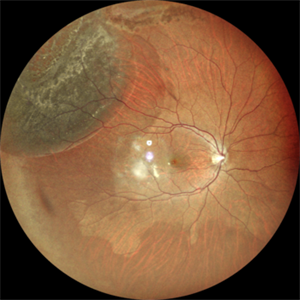

Bullous Rhegmatogenous Retinal Detachment with Macula off

Jan 11 2023 by Vaidehi Sathaye

Fundus photograph of RE of a 64 yr male with RE Superotemporal bullous Rhegamatogenous Retinal Detachment with macula-off

Photographer: Dr. Vaidehi Sathaye

Imaging device: Mirante

Condition/keywords: bullous retinal detachment, macula-off